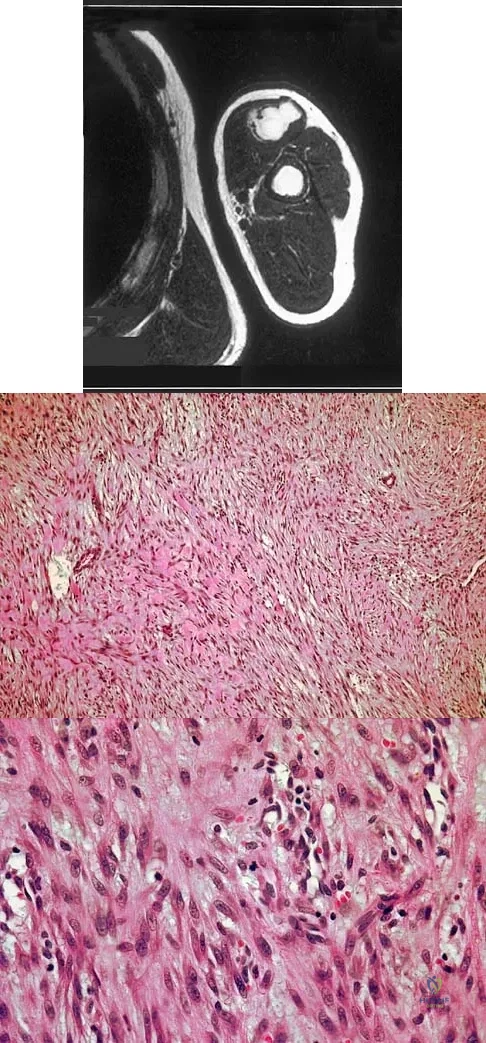

Question 98

A 13-year-old boy has had a painless mass in the arm for the past 2 months. An MRI scan and biopsy specimens are shown in Figures 46a through 46c. What is the most likely diagnosis?

Explanation